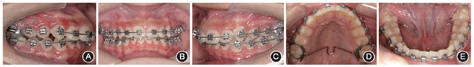

面像(2)二期矫治:粘接直丝弓固定矫治器,依次使用0.305 mm(0.012英寸)、0.406 mm(0.016英寸)、0.457 mm(0.018英寸)镍钛丝及0.457 mm(0.018英寸)澳丝排齐上下牙列。上颌横腭杆扩弓2 mm协调牙弓宽度。口外弓支抗条件下,利用前牙散在间隙和上颌扩弓间隙,远移13、23,建立尖牙中性关系(图4,5)。

患者矫治9个月时(二期矫治)口内像,示上下牙弓宽度匹配,尖牙关系改善 A:右侧

像;B:正面

像;C:左侧

像;D:上颌

面像;E:下颌

面像

面像上、下颌弓丝换至0.483 mm×0.635 mm(0.019英寸×0.025英寸)不锈钢方丝,将矫治弓丝末端回弯。皮链连扎上、下牙列,防止上下颌前牙出现间隙,并使上、下牙列各自成为一个整体。上颌采用口外弓支抗配合水平牵引,减小垂直向分力,维持现有下颌生长方向。口外弓与头帽弹性牵引,每侧牵引力约2.94 N,每日配戴时间≥12 h。